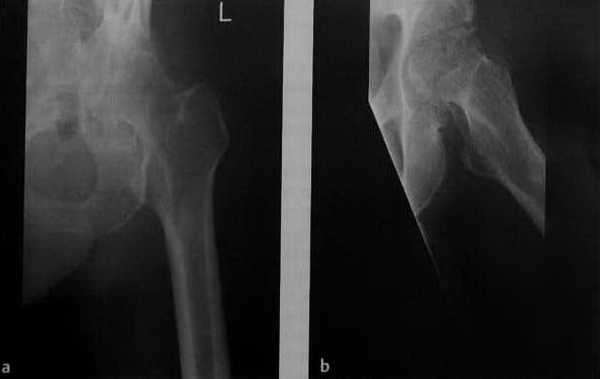

а-с Септический артрит (пиогенный артрит)у мужчины 43 лет с алкоголизмом в анамнезе и циррозом печени. Болевой синдром вследствие инфекции левом тазобедренного сустава в течение двух недель, интермиттирующая лихорадка и высокий уровень СОЭ: а, b) Рентгенологическое исследование левого тазобедренного сустава в двух плоскостях. Выраженная остеопения вокруг сустава, сужение суставной щели и начинающаяся деструкция головки бедренной кости;

с) МРТ. Последовательность STIR демонстрирует выпот в полости сустава, абсцесс в подвздошно-поясничной области и отек костного мозга в головке бедренной кости и вертлужной впадине.